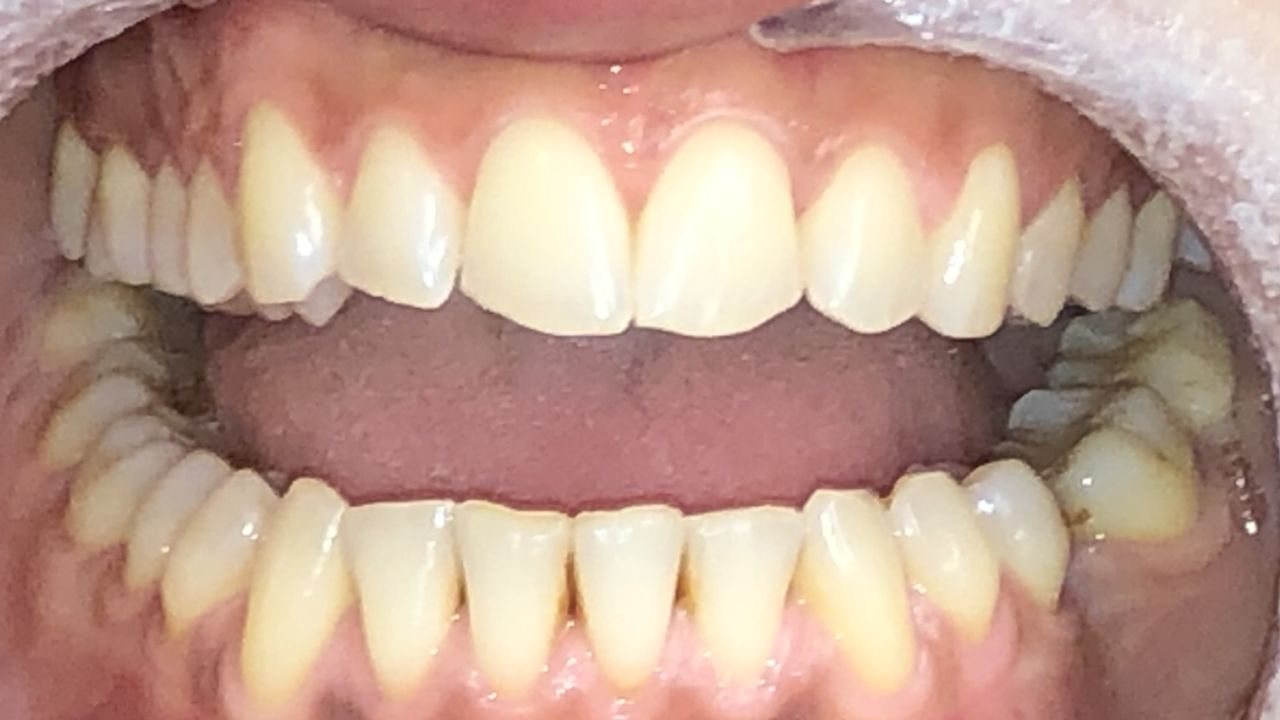

Foto e video

• M

Il Dottor Luca Strazioso ha qualità rare; mi ha ascoltata attentamente sin dal primo appuntamento, con la sua pazienza, competenza e professionalità durante ogni seduta ha ricostruito il mio sorriso, mi ha ridato la sicurezza che ormai avevo perduto. Posso affermare di essere rinata grazie alle sue mani, alla sua intelligenza e sensibilità. Inoltre, la Signora Antonella, assistente alla poltrona, è assolutamente insostituibile e generosa. Infinitamente grata ad entrambi.

• Studio Dentistico LUCA STRAZIOSO implantologia  •